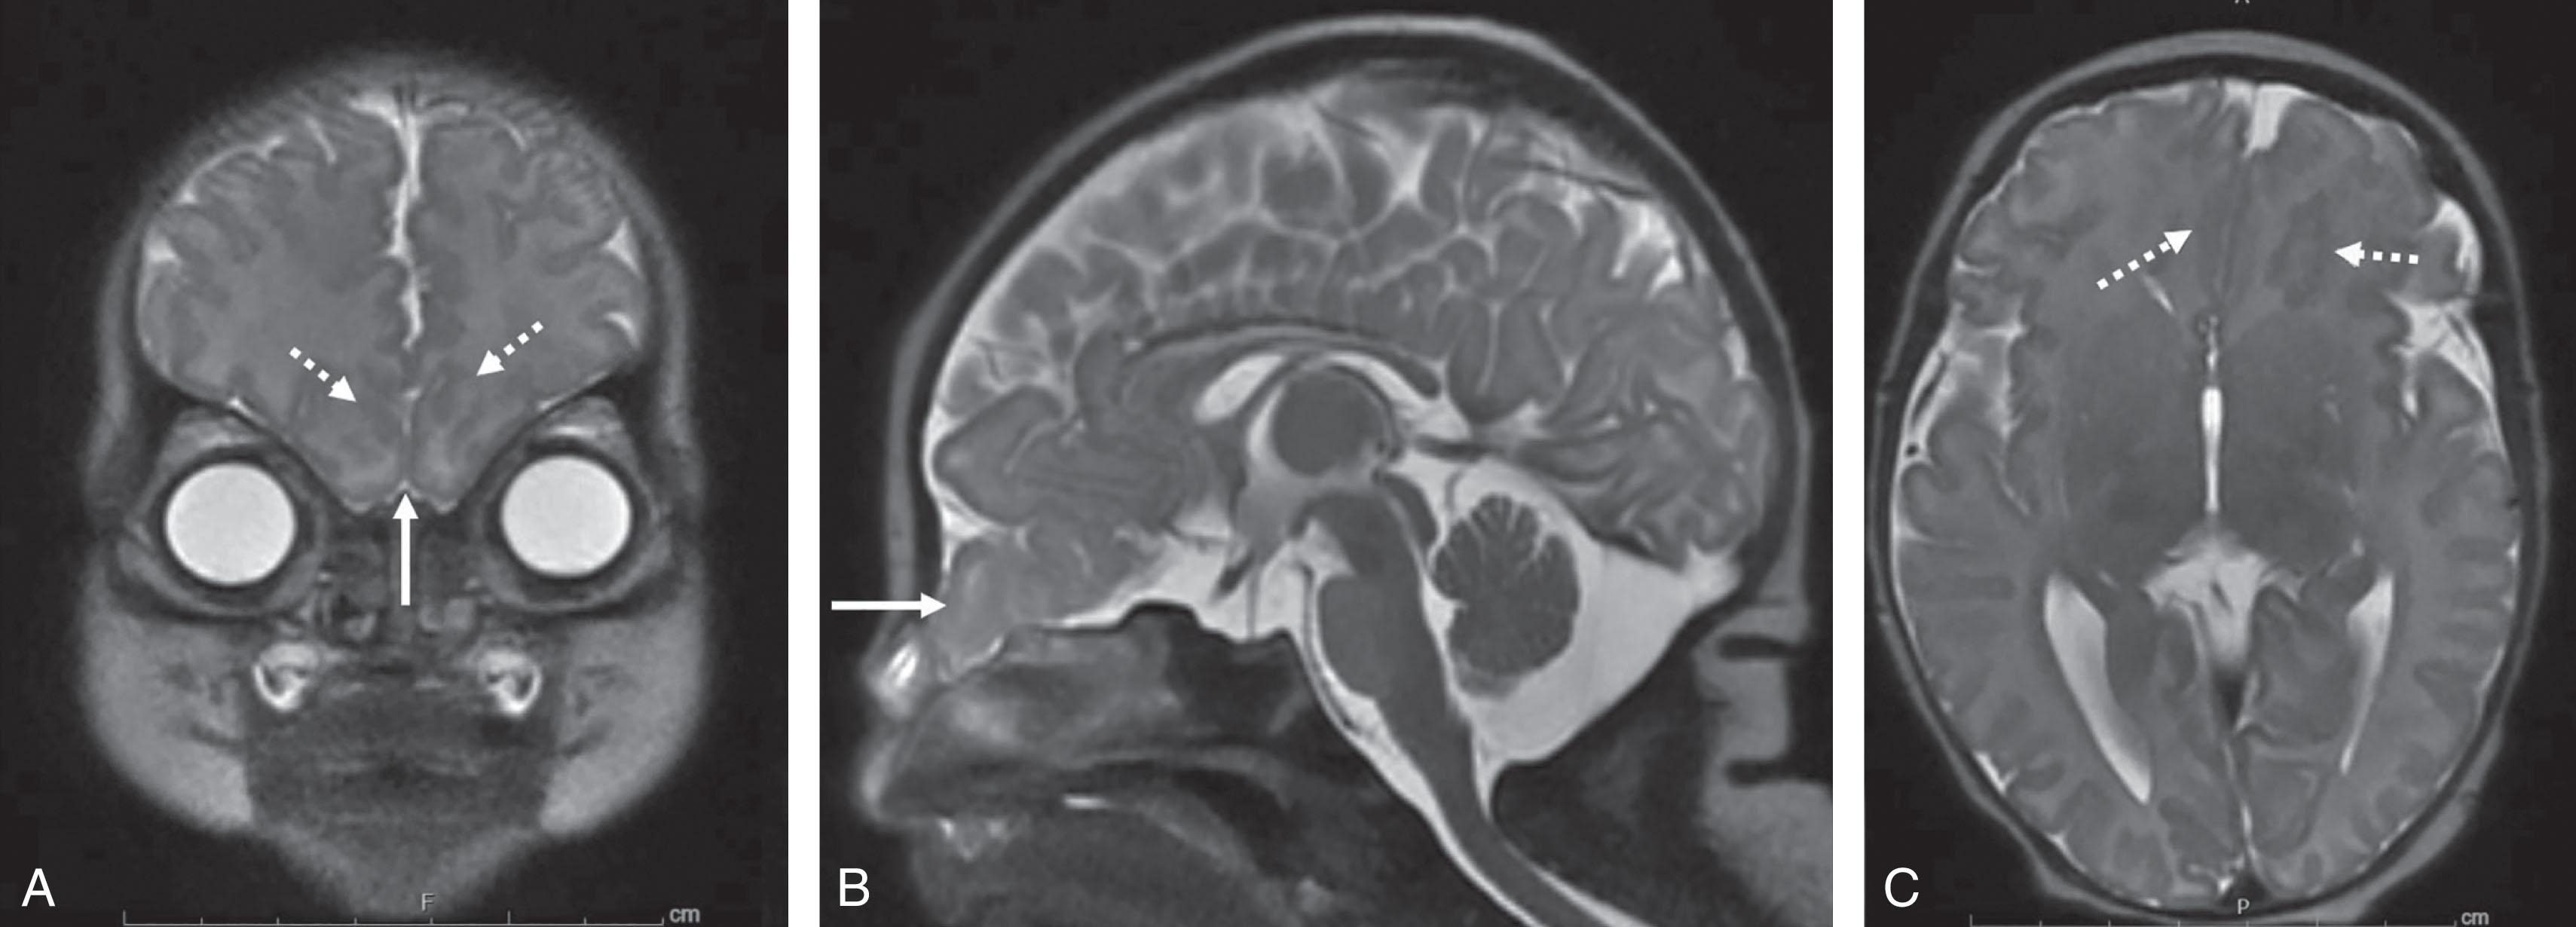

Fig. 1.10, Fronto-ethmoidal encephalocele. T2-weighted images (A, coronal; B, sagittal; C, axial) of a newborn with fronto-ethmoidal encephalocele with herniation of bilateral inferior rectus gyri ( solid arrows , A and B) and bilateral inferior frontal polymicrogyria ( broken arrows , A and C).